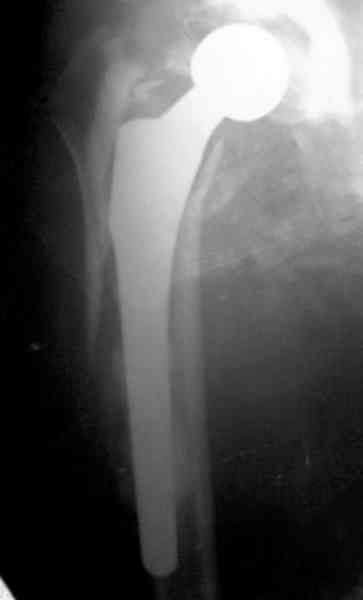

Приглашенный хирург установил ревизионный вариант бедренного компонента без замены ацетабулярного компонента, что осложнилось нагноением и свищами на уровне сустава и средней трети бедра. После двухгодичного безуспешного лечения перевязками и антибиотиками больная обратилась к нам на консультацию.

Повторная операция по удалению тотального протеза с irrigation&debridment, канал после очистки цемента обильно промыт и рассверлен римером.

№3-6 снимки с осложнением

и последние снимки.